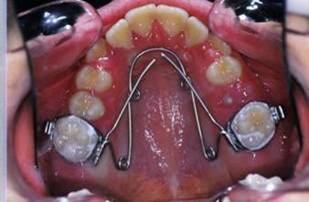

la suite de documents, comme vous allez le voir le premier moyen est un qh, mais quelle sera la suite?

1- RDV 1: QH

2- RDV 2 : Commencer avec ecran buccal + exercice de respiration

3- Quant elle est capable de garder oral screen toute la nuit je considere que la batail est gagnee

4- Collage de l'arcade sup, presque 6 mois apres et voici le photo apres seance de college